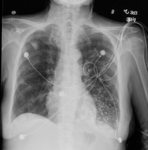

A. Portable upright chest x-ray before aspiration; B. Chest x-ray 1 hour after aspiration, showing bilateral diffuse alveolar infiltrates, worse at the bases on the right side

From the collection of Dr Henri Colt